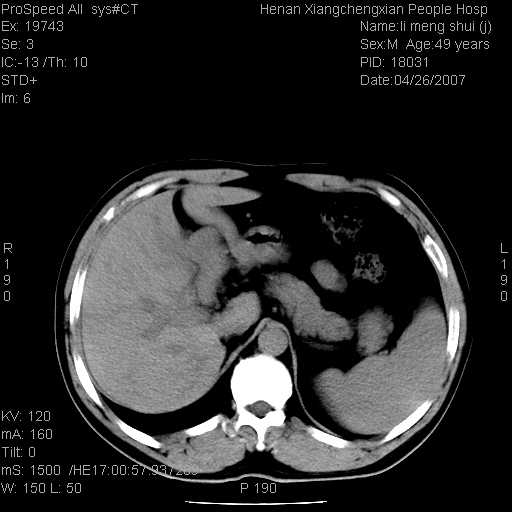

| 患者,男,49岁, 腹疼伴恶心\\呕吐20天,20天前无明显诱因出现右上腹部疼痛,钝疼,无放射,伴恶心\\呕吐,不伴发热.患者不愿增强. b超:肝脏右叶实性占位. ct:肝脏右叶可见一巨块状圆形低密度影,大小约93mm*84mm,其内可见点状高密度影,胆囊、胰腺、脾脏大小、形态及密度未见异常,腹膜后间隙未见肿大淋巴结影。 印象:肝脏右叶巨大肿块,性质待定,建议增强并穿刺活检进一步确诊。 ct平扫: ![]() ![]() ![]() ![]() ![]() ![]() ![]() ![]() ![]() ![]() ![]() ![]() ![]() ![]() ![]() ![]() ![]() 肝脏右叶肿块ct引导下穿刺活检术 患者于16时05分仰卧于ct检查台上,首先行肝脏ct扫描确定进针位置、深度、角度。在局麻下行ct引导下肝脏右叶肿块穿刺活检术。常规消毒、铺巾、局麻。在ct引导下使活检针经右侧腋中线、第9肋间隙垂直胸壁进针90mm,针头进入病变预定位置。在病变预定位置多点、多方向抽取小米样病变组织多块,涂片五张送病理检查。术后穿刺点局部无出血,未出现腹腔积液等并发症。术中及术后患者生命体征稳定,手术于17时10分成功完成。患者安返病房。 穿刺片 ![]() ![]() ![]() ![]() ![]() ![]() ![]() ![]() ![]() ![]() ![]() ![]() ![]() ![]() ![]() ![]() 病理结果肝细胞癌 ![]() 原贴地址:http://www.radinet.com.cn/forum_view.asp?forum_id=4&view_id=24130 ok |